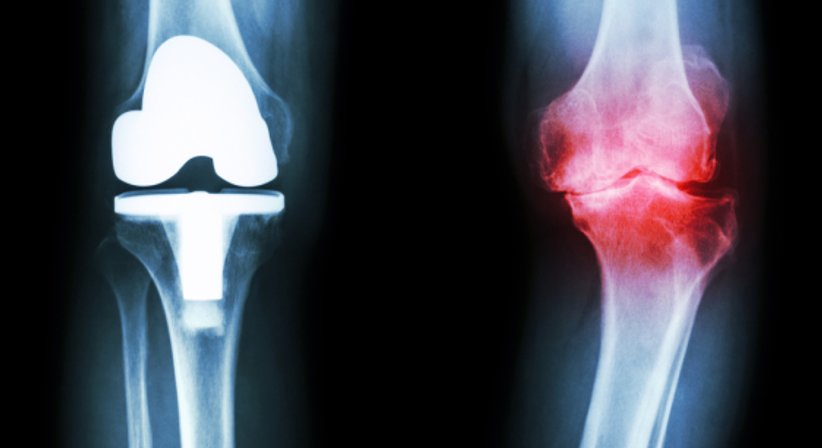

Knieprothese

Bei Patienten mit massiver Arthrose vom Kniegelenk, bei welchen konservative Therapien nicht mehr wirksam sind, ist die Implantation einer Knieprothese sinnvoll, um die Schmerzen im Knie dauerhaft zu beseitigen und die Mobilität und folglich auch die Lebensqualität zu verbessern.

Bei einer Knieprothese handelt es sich um eine implantierte Prothese, die das Kniegelenk ganz oder teilweise ersetzt. Eine Knie-Teil-Prothese kommt prinzipiell bei Patienten in Frage, bei welchen die Arthrose lokal begrenzt ist bzw. wenn nur die Innen- oder Außenseite vom Gelenkknorpel abgenutzt ist; der gut erhaltene und schmerzfreie Anteil vom Kniegelenk wird bei der Implantation einer Knie-Teil-Prothese nicht tangiert.